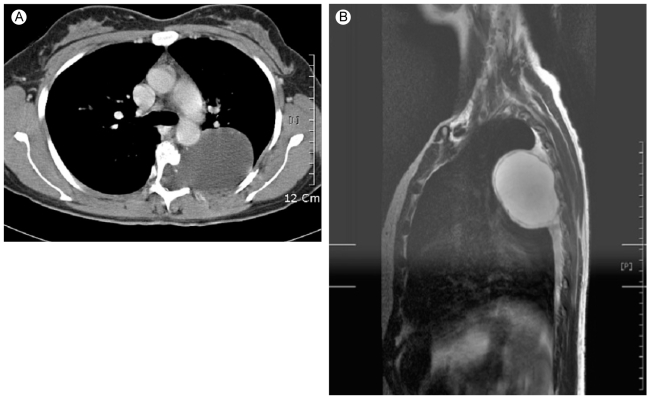

Figure 4

(A) A 7 cm low attenuation mass in the left paraspinal space, eroding the left side of T4-T7 vertebrae and extending into the spinal canal through the T5-6 neural foramen on chest CT. (B) An 80 × 58 × 55 mm homogenous, cystic mass in the left paraspinal space and the neural foramen at the left T5-6 level on chest MRI.

A 41-year-old woman came to the hospital for the evaluation of a lung mass found on a chest radiograph. The patient had no signs or symptoms. However, on physical examination, widespread café-au-lait spots, cutaneous neurofibromas (Fig. 1A), axillary frecklings and reddish brown spots on the iris (Lisch nodules) (Fig. 1B) were present, consistent with the diagnosis of NF-1 [1]. Among the family members, a 14-year-old daughter and 12-year-old son had similar manifestations of NF-1 (Fig. 2). A large mass and a scoliosis were noted on a chest radiograph (Fig. 3). The chest CT and MRI (Fig. 4) showed a 7 cm homogeneous cystic mass with a thin wall in the left paravertebral area, extending into the spinal canal through the T5-6 neural foramen. Clear fluid was withdrawn by needle aspiration and the diagnosis of an intrathoracic meningocele was made. Regular follow-up with periodic imaging was recommended without surgical treatment.